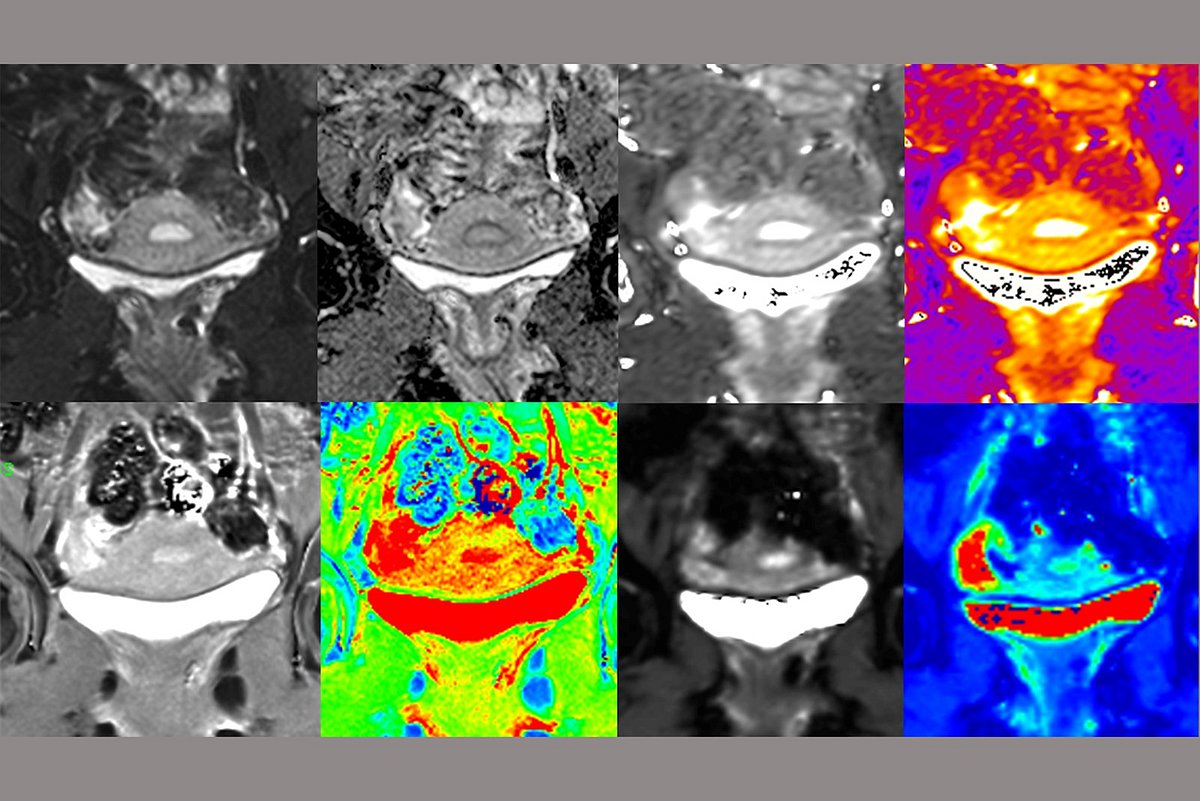

Im Rahmen der Studie sollen Veränderungen an der Gebärmutter mittels Magnetresonanztomografie (MRT) gemessen werden. Die Untersuchung ist schmerzfrei; eine Einnahme von Medikamenten oder Kontrastmitteln ist nicht erforderlich. Neben der MRT-Untersuchung und einer persönlichen Anamnese erfolgt ein körperlicher Check-up inklusive gynäkologischer Ultraschalluntersuchung. Der zeitliche Aufwand beträgt insgesamt circa vier Stunden, verteilt auf zwei Termine an bestimmten Zyklustagen. Alle Probandinnen haben die Möglichkeit, die entstandenen Bildgebungen ihrer Gebärmutter und ihrer Eierstöcke im Hinblick auf mögliche Erkrankungen kostenfrei prüfen zu lassen. Für die erfolgreiche Durchführung der Studie ist auch die Teilnahme von gesunden Mädchen und Frauen erforderlich, die keine oder nur leichte Regelschmerzen haben. Denn: Um die Früherkennung der Adenomyose mittels MRT nach wissenschaftlichen Standards zu untersuchen, müssen die Bildgebungsdaten der Betroffenen mit denen von beschwerdefreien Probandinnen verglichen werden.